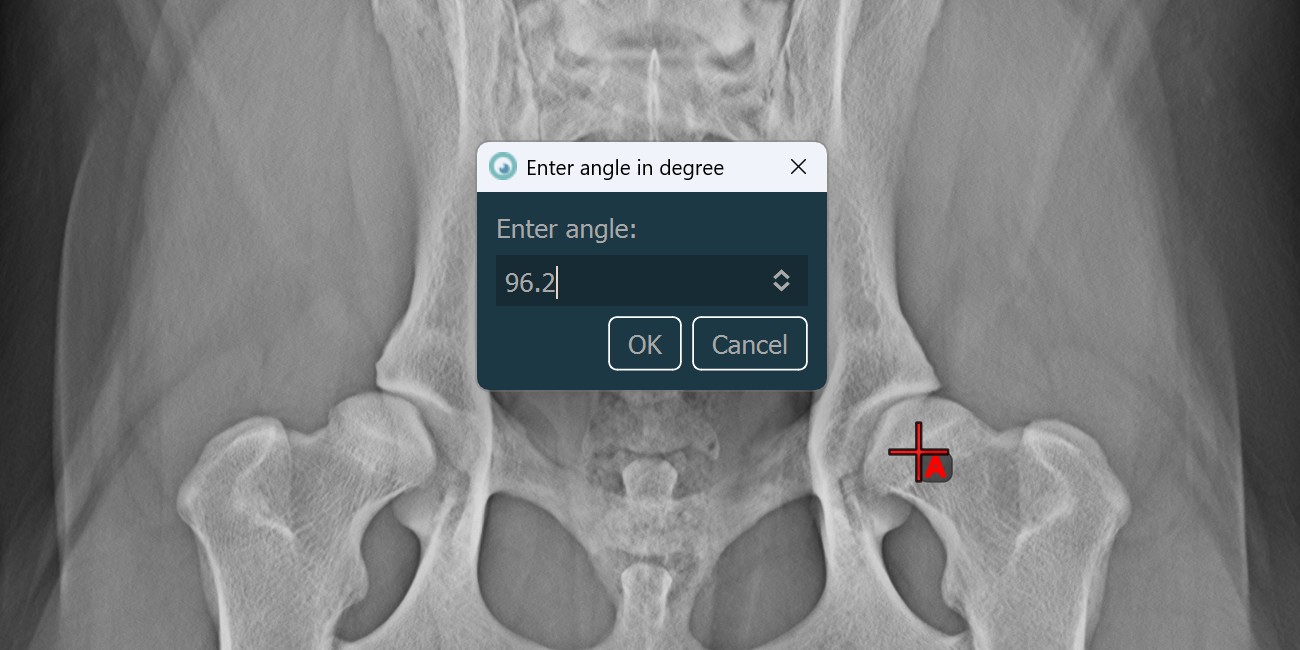

Fixed Angle¶

Use the Fixed Angle tool to create an angle of lines with a fixed arc. Only the orientation of the angle on the scene can be modified later.

Select the

Fixed Angletool from the left toolbar and assign it to one of the available mouse buttons.Select a line from the ones already drawn on the scene, or mark the start point of the initial side of the angle.

Specify the desired angle in degrees and press

OKto continue.

Mark the end point of the initial side of the angle to complete the measurement. If the user selected a line in the second step, the measurement is automatically completed. The terminal side of the angle is drawn based on the orientation of the initial side and the specified angle in degrees.